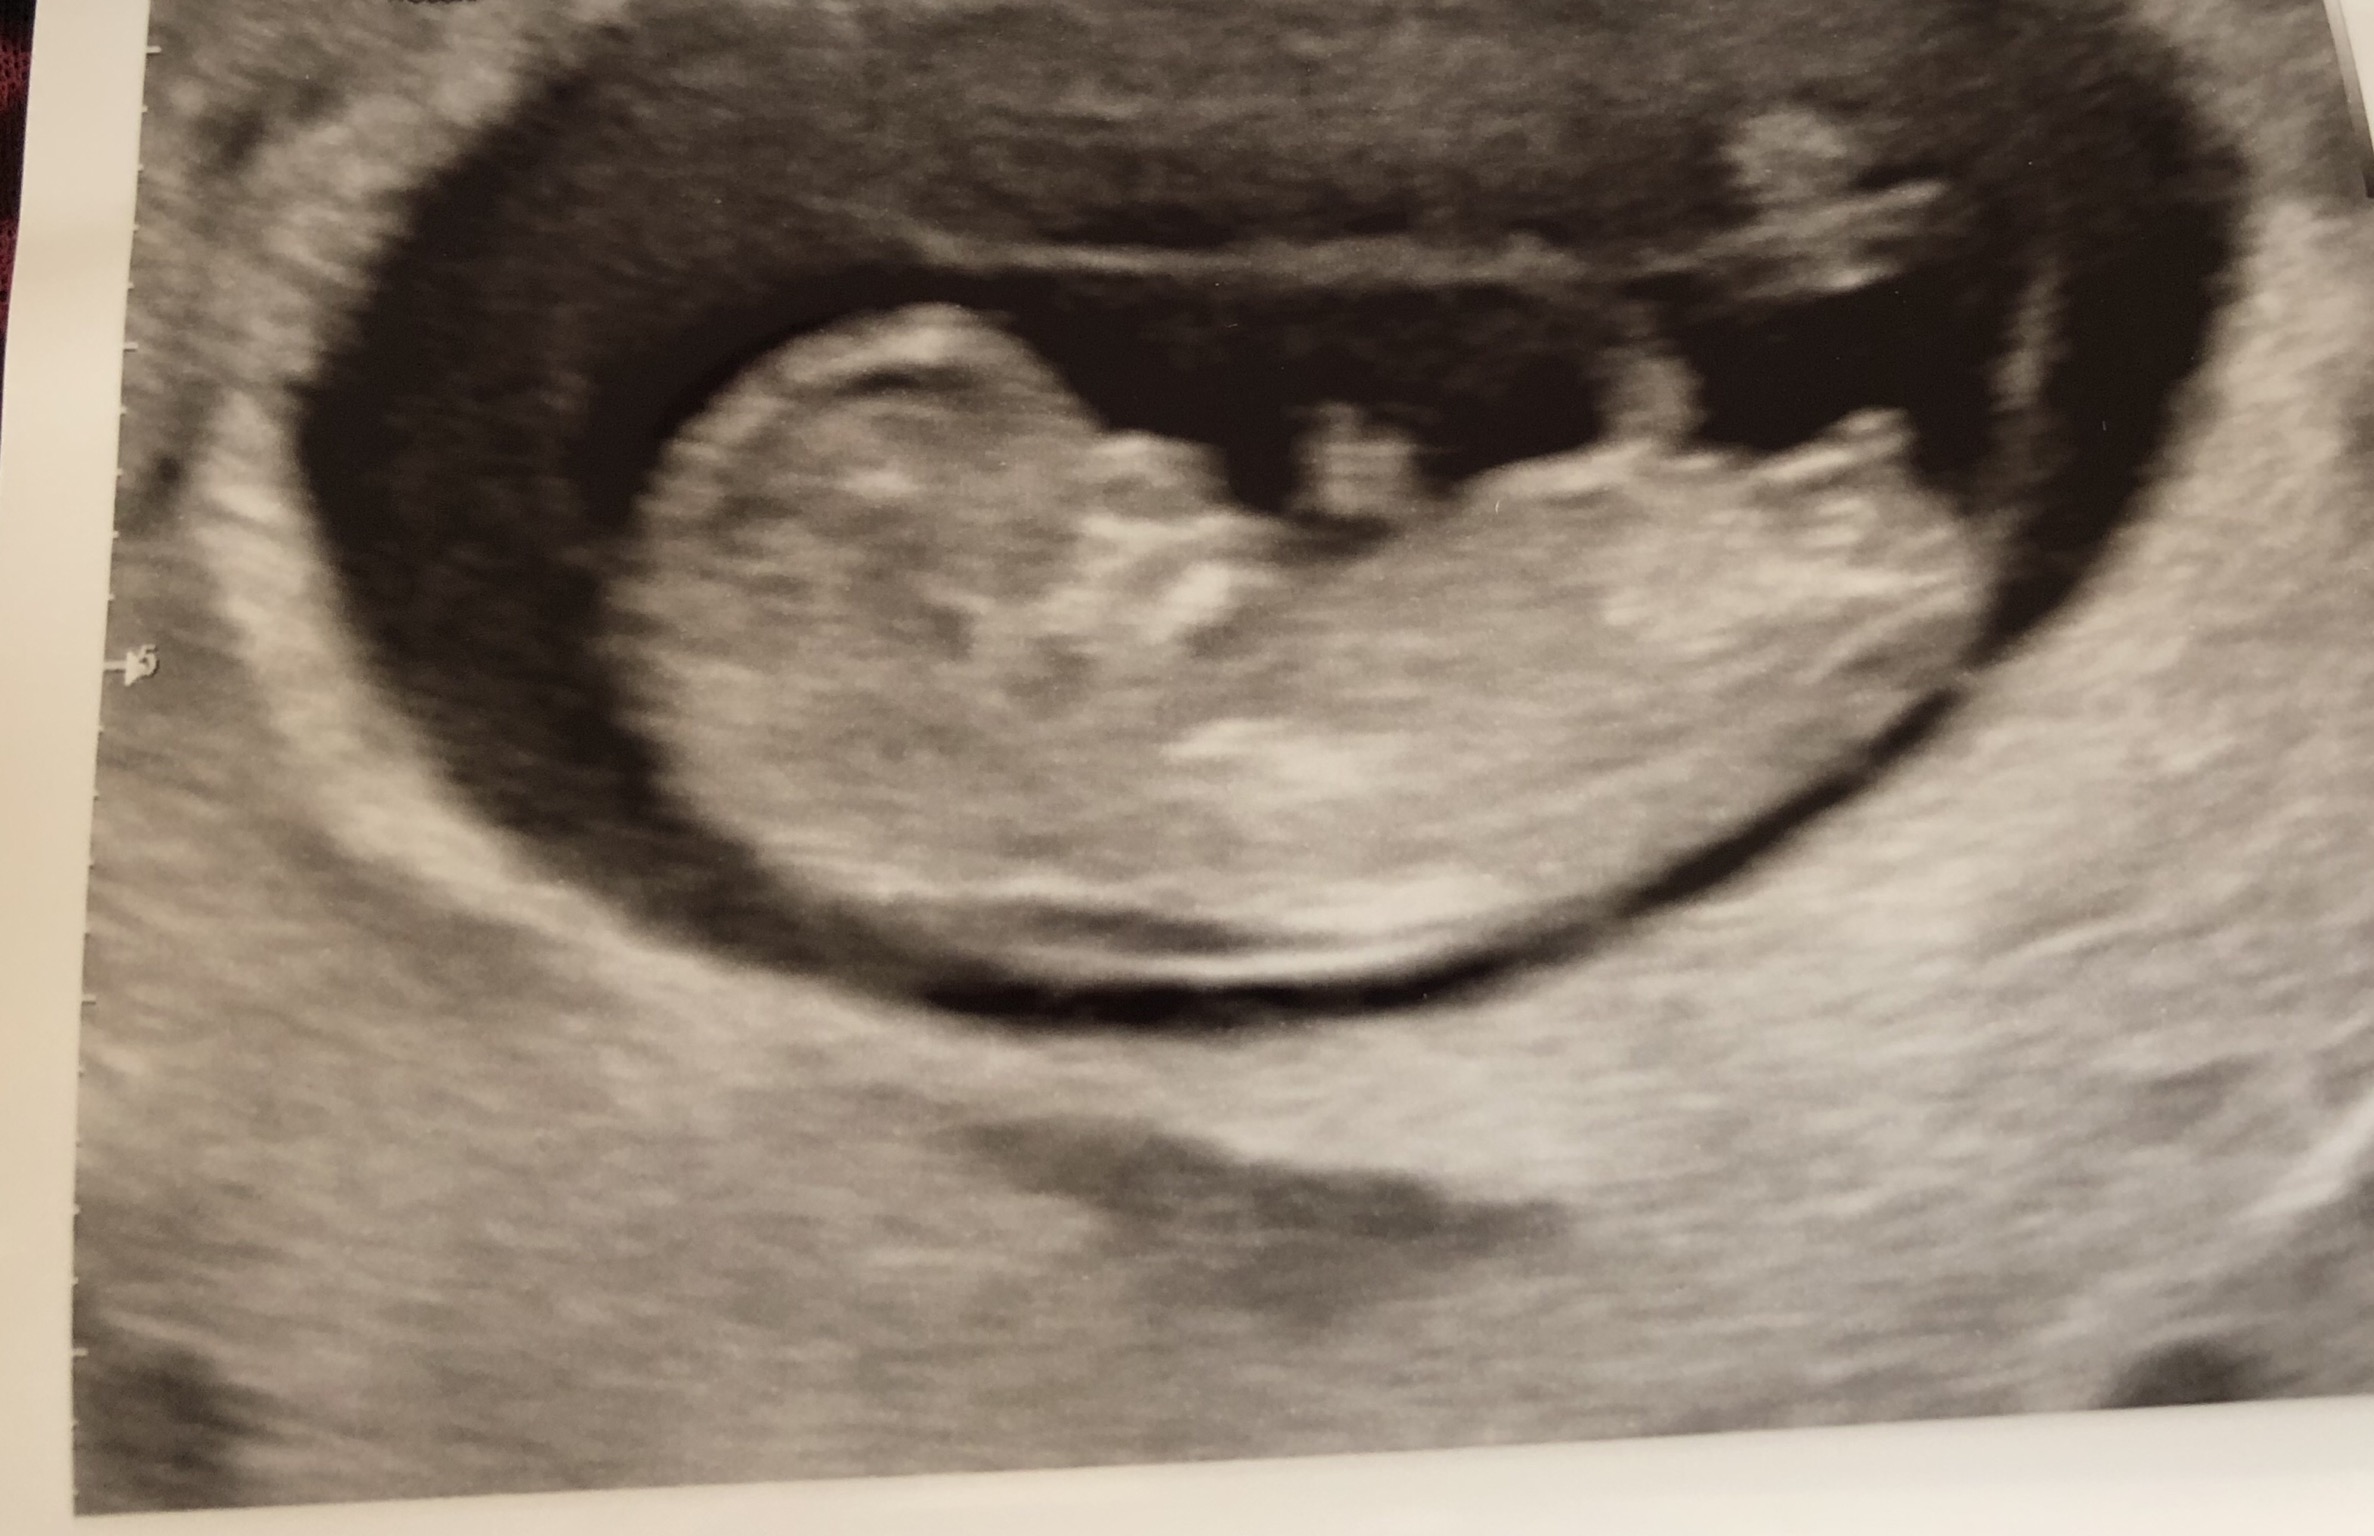

خدایا ممنونم بهم بچه های سالم دادی خدای خوبم مرسی که مث همیشه چشمتو رو تمامممم بدی هام بستی و خواستمو برآورده کردی...من دیگه فقط مامان پریا نیستم من الان مامان پریا و علی هستم❤❤❤